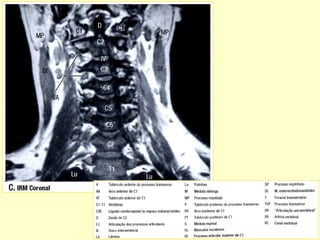

Pequeno hematoma epidural C7-T1

Pequeno edema/hematoma de medula cervical C1-C2

ANATOMIA RADIOLÓGICA CERVICAL

Anatomia radiológica